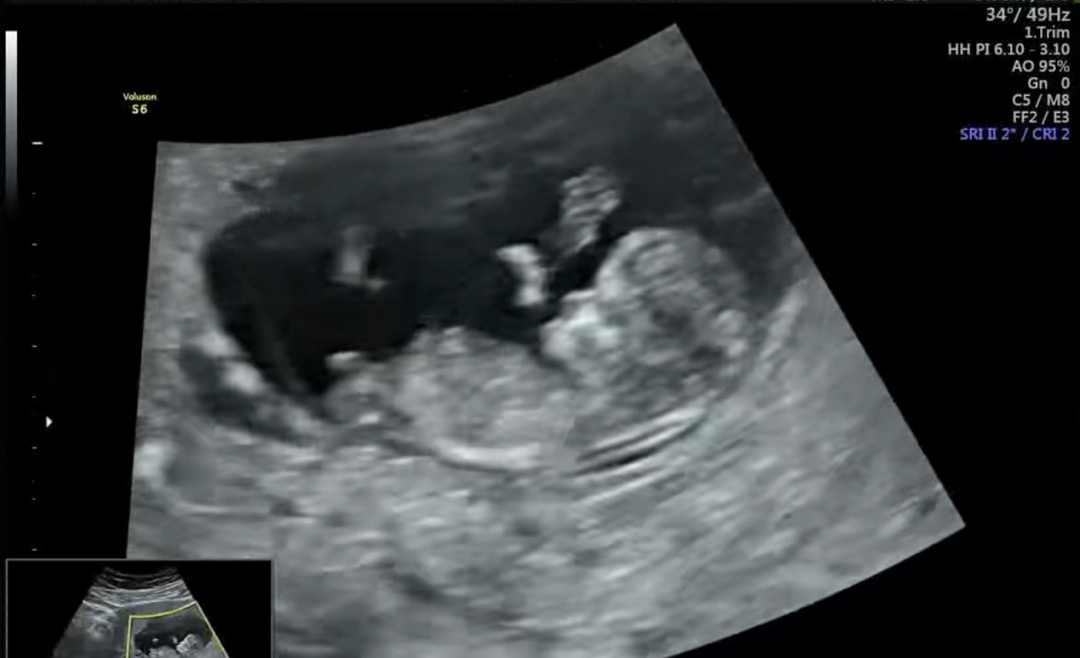

둘째 각도법 봐주실 수 있을까요?

성별이 너무 궁금해요 ㅠ